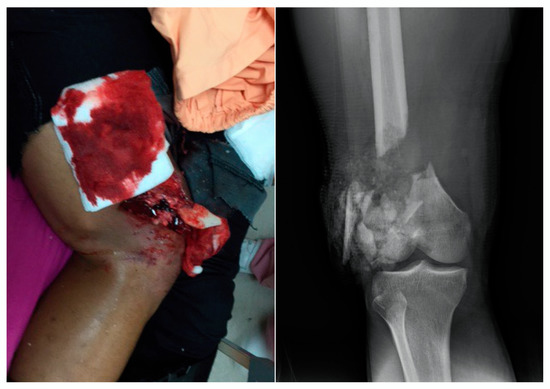

2.1. Case Report